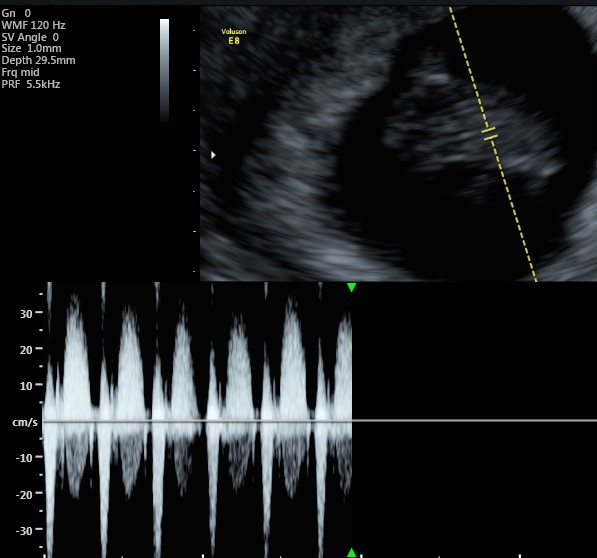

Con l’ecografia, che, a seconda dell’epoca gestazionale e dalla posizione dell’utero, può essere fatta sia per via addominale che transvaginale, potremo vedere un piccolo fagiolino con al suo interno il “cuoricino” che batte, facendoci realizzare che quei pochi millimetri di vita e di amore sono l’evento più sconvolgente della propria vita, e da qui in poi niente sarà più come prima.

Tipicamente la prima ecografia va fatta dopo la 6° settimana per evitare di non vedere nulla e rimanere conseguentemente delusi.